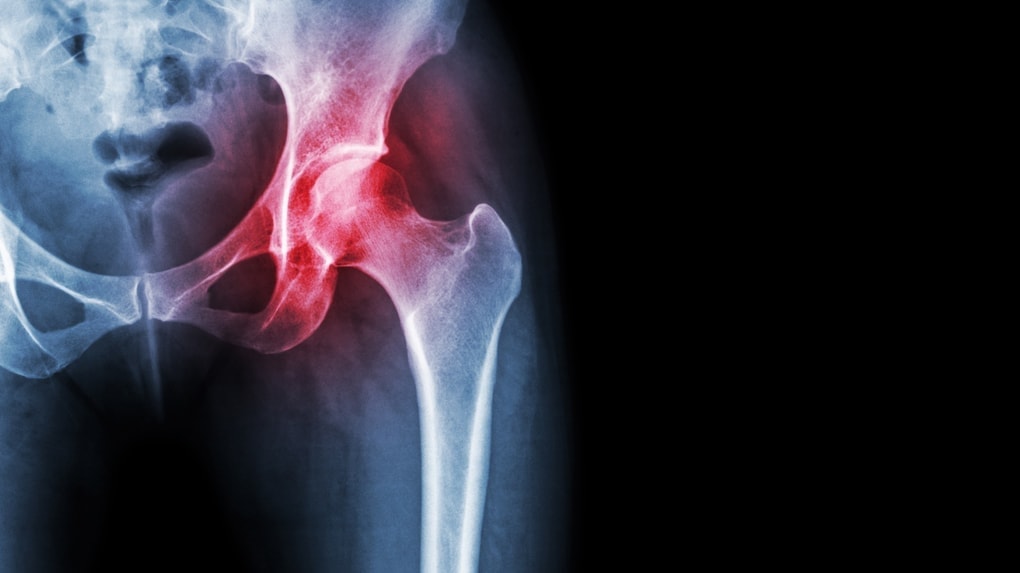

• 骨盤や骨格のゆがみからくる腰痛

骨盤からくる腰痛

骨盤・骨格のゆがみが原因の場合は、ズレた骨の位置を元に戻すことで、腰痛が和らいだり改善に至ります。

特に骨盤や背骨のゆがみは影響が大きいですから、腰痛に悩む姿勢が悪い人は軽視しない方が良いでしょう。

と考えた時にとても重要になってくるのは「骨盤」です。

この負担を支えるために腰椎と骨盤はとてもとても面積の広い安定した関節の構造になっています。

しかし、安定しているとはいえ背骨を乗せている骨盤が、もし傾いていたとしたらどうでしょう?

腰に負担のかからない理想の骨盤の角度とは?

実は骨盤には背骨にかかる負担を最小限にするための理想の角度というものがあります。

まず骨盤が土台だと考えると、その上に「頚椎」「胸椎」「腰椎」と呼ばれる24個の背骨が、だるま落としのように重なり、さらにその上には重い頭部(約6キロ)が乗っているタワー型の構造になっています。

もし骨盤という土台が傾いてしまっていたらどうでしょう?背骨は頭を支えることなどできずに崩れてしまいます。